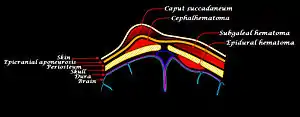

Caput succedaneum is a neonatal condition involving a serosanguinous, subcutaneous, extraperiosteal fluid collection with poorly defined margins caused by the pressure of the presenting part of the scalp against the dilating cervix (tourniquet effect of the cervix) during delivery.

It involves bleeding below the scalp and above the periosteum.[1]